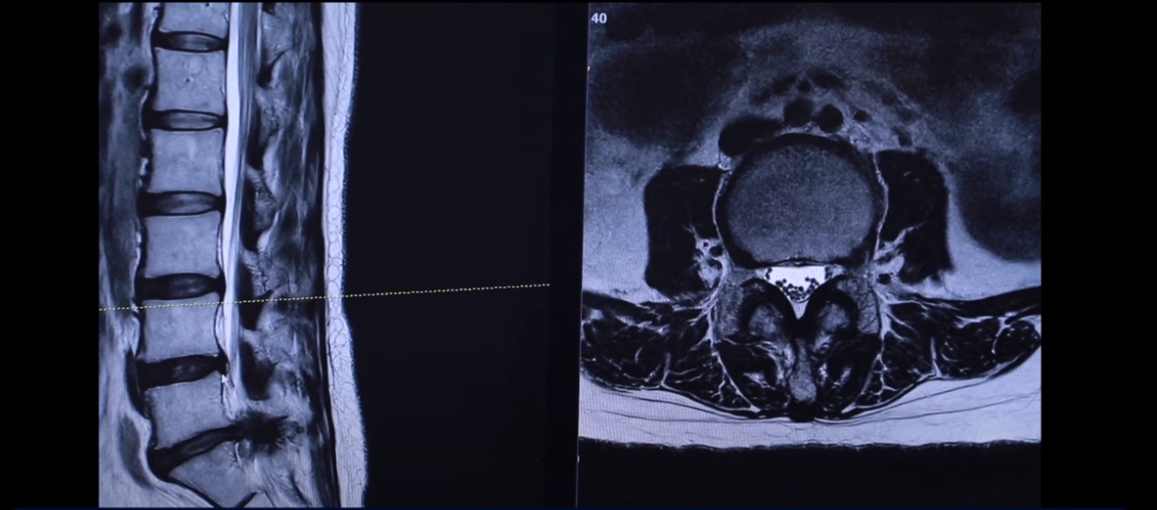

43세 여자 허리 디스크 파열 환자분 MRI 보도록 하겠습니다. 이분은 파열이 어마어마하게 심합니다. 세 마디에 퇴행성 디스크가 있는데 5번 1번을 보면 위와 아래로 밀려 올라가 있죠.

터져서 밀려나온 디스크 수핵이 위와 아래로 밀려 나가 있습니다. 보시면 이쪽이 왼쪽입니다. 환자의 왼쪽을 완전히 덮어버렸죠.

그래서 역시 이분 증상은 왼쪽 다리 방사통입니다. 왼쪽 다리 방사통과 왼쪽 다리 마비 증상 운동 마비는 심하지 않고 감각 마비가 심합니다. 발가락 발바닥 이런 데 감각을 느끼지 못하는 감각 마비 증상이 있습니다. 사실은 이 정도면 운동 마비도 있을 만한데 예를 들면 까치발이 안 된다든가 아니면 족하수 증상이 있다든가. 그런데 그런 운동마비 증상은 없으셨습니다. 너무너무 많이 터졌기 때문에 수술 병원에 가서 즉시 전신 마취를 해서 수술을 해야 된다고 듣습니다.